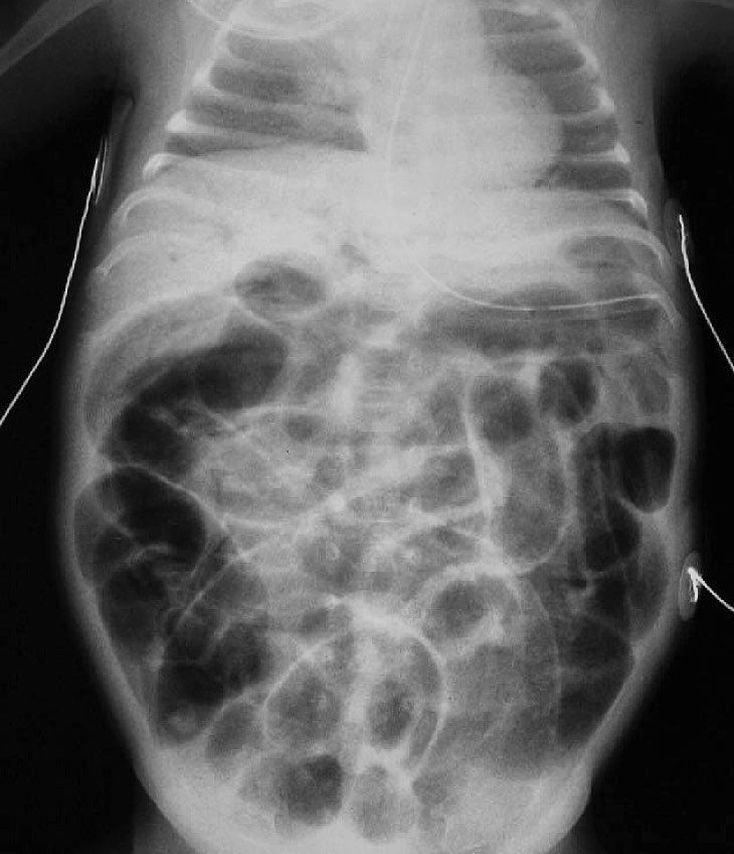

This is a classic presentation of a disease known as Necrotising enterocolitis (shortly, NEC). NEC typically occurs in the second to third week of life in premature babies, is characterized by variable damage to the intestinal tract, small and/or large bowel, ranging from mucosal injury to full-thickness necrosis and perforation. The cause is unclear but is probably related to a complex interplay between intestinal ischaemia, injury, and infection.This radiograph demonstrates the classic intramural gas (pneumatosis intestinalis) appearance of necrotising enterocolitis. The air within the intestinal wall is though to be due to gas produced by overgrowth of enteric bacteria. Treatment consists primarily of supportive care including providing bowel rest by stopping enteral feeds, gastric decompression, correction of electrolyte abnormalities, regulation of BP, and prompt antibiotic therapy.

Can't really find any double lines of the wall in this (maybe someone could point to a few), but that's true, the obstruction like this is one of the x-ray stages